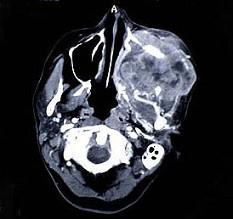

问题 以下关于上颌窦癌(见图)的叙述,哪项是错误的()

选项 A.以鳞状细胞癌为最常见 B.早期无症状而不易发觉 C.肿瘤发生部位不同可出现不同临床症状?(如鼻塞、复视、张口受限等) D.早期即有明显的骨质破坏 E.远处转移较少见

答案 D